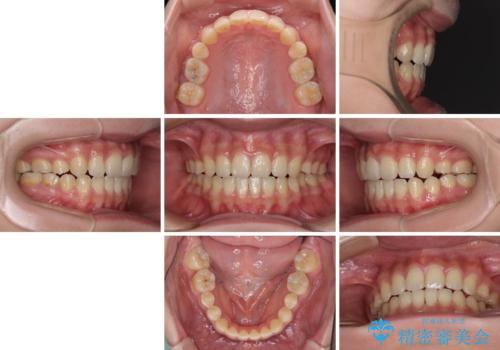

話しにくいオープンバイト ワイヤー装置による抜歯矯正治療

- 前歯のオープンバイトを気にして来院された患者様です。

上下前歯の前後位置が大きくずれていたため、上顎左右第一小臼歯2本を抜歯してワイヤー装置による矯正治療を行うこととしました。

オープンバイトの原因は舌の突出癖であり、癖が改善されないと治療経過に影響を及ぼすため、舌のトレーニングを指示しました。

なかなか癖が改善されず、トレーニングも断続的に行ったため、治療期間は長期化しました。